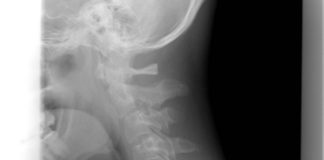

Wysłali go do domu ze złamanym kręgiem szyjnym

41-letni John Barnet po wypadku motocyklowym miał złamania mostka i kręgu w odcinku szyjnym kręgosłupa. Przez sześć godzin przebywał Dr. Everett Chalmers Regional Hospital...